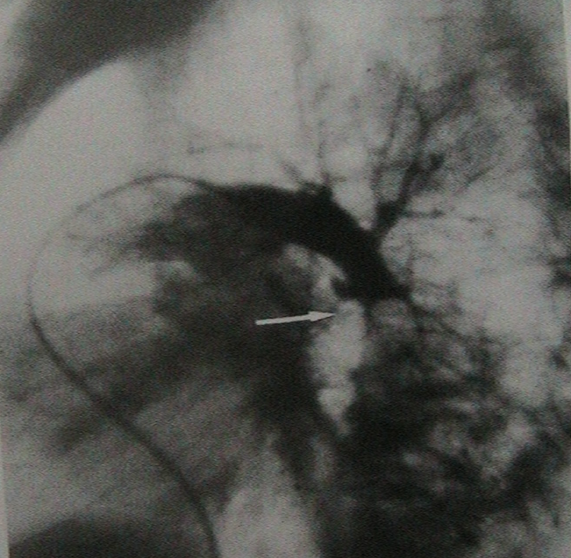

- Аортография с артериографией аберрантного легочного сосуда